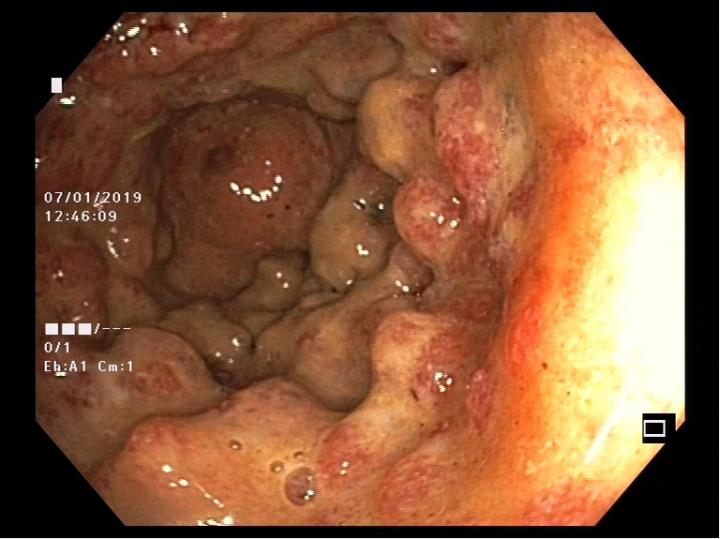

There are different forms of inflammatory bowel disease (IBD) - Crohn's disease (which affects different segments of the entire intestinal tract) and ulcerative colitis (which affects the large intestine). These conditions affect about 30 people per 100,000 of the European and North American populations. Over the last 10 years the incidence of IBD in Switzerland has sharply increased: in 2004 there were about 12,000 patients compared with 20,000 in 2014. Since IBD usually starts before the age of 35, with major ongoing limitations for the quality of life and ability to work, the conditions also have severe social and economic consequences.

New results have now been reported on the relationships of intestinal bacteria in IBD patients by the research team led by Andrew Macpherson, Bahtiyar Yilmaz und Pascal Juillerat in the Department of Biomedical Research in the University of Bern and the University Clinic of Visceral Surgery and Medicine of the Inselspital. They have discovered that changes of particular species of intestinal bacteria lead to severe relapsing disease resistant to therapy and even make the return of the disease more likely in patients whose active segments of Crohn's disease have been surgically removed. The work is being published in the journal Nature Medicine .

The researchers examined the relationship between the intestinal microbes, the way in which the disease developed, and how it responded to treatment in 270 patients with Crohn's disease, 232 patients with ulcerative colitis and 227 healthy individuals. The intestinal samples were provided from two large patient cohorts, the Swiss IBD cohort led by Professor Gerhard Rogler of the University Hospital of Zürich, with major contributions from many different Swiss hospitals and Gastroenterology community practices, and a separate cohort of patients from the Gastroenterologists of the Inselspital Bern. Dr. Bahtiyar Yilmaz, the co-first author of the study commented, 'The availability of this range of material from two separate groups of patients studied over many years with unprecedented documentation of all the clinical details by Swiss gastroenterologists and the staff of the Inselspital Bern made our study unique'.